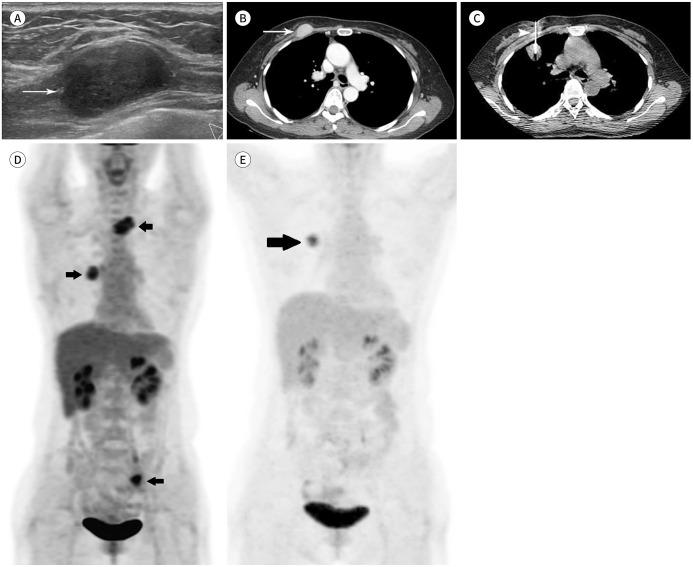

Percutaneous transthoracic needle biopsy (PTNB) is a minimally-invasive procedure that is an indispensable tool for evaluating pulmonary lesions. Though extremely rare, tumor seeding of the pleura and chest wall can occur as a complication. Given that the breast is located anterior to the thorax, needle tracking through the breast is inevitable when PTNB is performed using the anterior approach. We describe tumor seeding of metastatic pulmonary ameloblastoma in the pectoralis muscle layer of the breast along the needle track of PTNB in a 51-year-old female presenting with a palpable lump in the right breast.

经皮经胸针吸活检(PTNB)是一种微创手术,是评估肺部病变不可或缺的工具。虽然极为罕见,但胸膜和胸壁的肿瘤种植可作为一种并发症发生。鉴于乳房位于胸部前方,当采用前入路进行PTNB时,针道穿过乳房是不可避免的。我们描述了一名51岁女性,因右乳可触及肿块就诊,在经皮经胸针吸活检针道的乳房胸肌层出现转移性肺成釉细胞瘤的肿瘤种植。